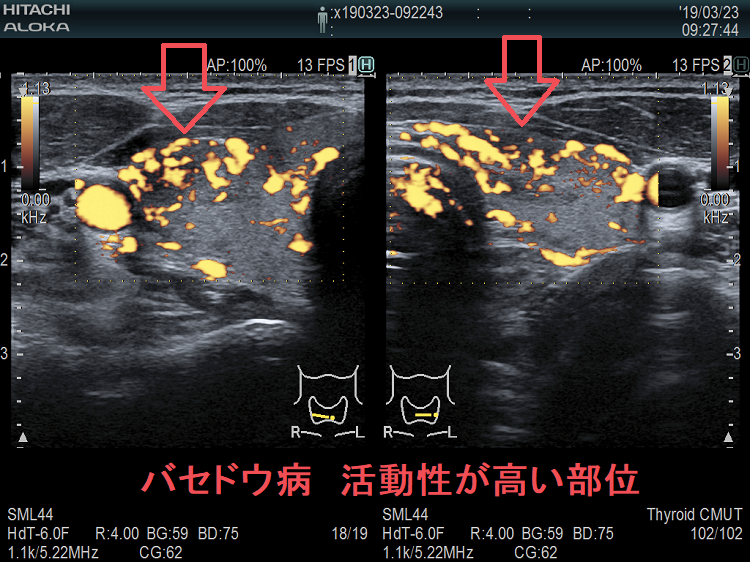

局所的に血流が多く、低エコーな領域

抗甲状腺薬投与により、甲状腺機能が正常に保たれているバセドウ病では、治療前の”火炎状血流増加”と呼ばれる甲状腺内部の異常血流増加が減少していきます。しかし、局所的に血流が多く、低エコーな領域は活動性が残存しています。(J Clin Ultrasound. 2005 Oct;33(8):381-5. doi: 10.1002/jcu.20157.)(Exp Clin Endocrinol Diabetes. 2013 Jan;121(1):1-5.)(AJR Am J Roentgenol. 1996 Jan;166(1):203-7.)

バセドウ病 局所的に活動性が高い部位

バセドウ病 局所的に活動性が高い部位(低エコー)

バセドウ病 局所的に活動性が高い部位 ドプラーモード

バセドウ病 局所的に活動性が高い部位 ドプラーモード(低エコー領域は局所的に血流が多く)